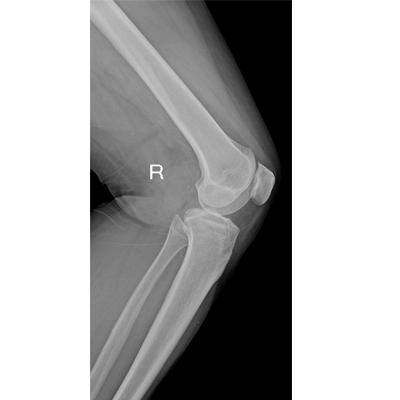

用于影像科、急診室、病房、ICU、手術(shù)室等多場(chǎng)景應(yīng)用。

● 數(shù)字化無(wú)線平板成像,操作簡(jiǎn)便,成像質(zhì)量高